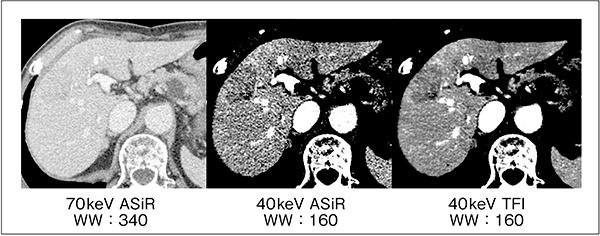

そこで,GEは,ディープラーニングを用いて,低ノイズかつ自然な質感を両立した画像を再構成することが可能なTrueFidelity Image(以下,TFI)を開発した。TFIは米国食品医薬品局(FDA)に承認された,世界で初めてのディープラーニング再構成法である。TFIをGSIと併用することにより,ノイズの影響を受けやすかった低keV画像などが非常に使用しやすいものとなり,病変部の視認性をより向上させることが可能となった(図2)。また,ノイズを大幅に低減することにより,低keVとnarrow windowの組み合わせによる低コントラスト強調に特化した画像を提供することも可能である(図3)。

図3 低keVとnarrow windowを組み合わせた低コントラスト強調画像(肝腫瘍)